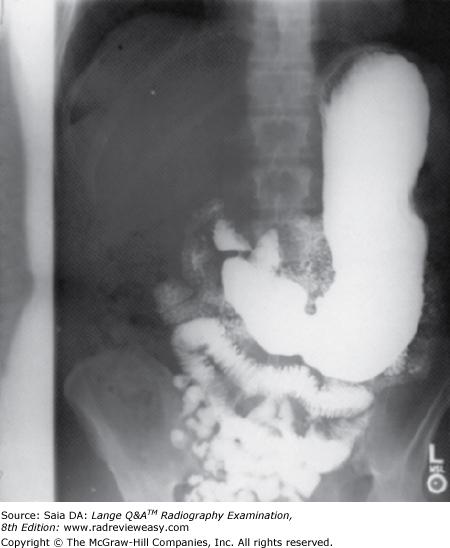

What is the correct critique of the CR image seen below?

A double exposure

B grid centering error

C incorrect AEC photocell

D inverted focused grid

-This is an example of both off-focus and lateral decentering errors. Note the asymmetric cutoff from right to left. The individual grid errors, as well as the result of both errors together, is summarized below. Off-focus errors: Grid cutoff will occur if the SID is below the lower limits, or above the upper limits, of the specified focal range. This type of error is also referred to as focus–grid distance decentering. Off-focus errors are usually characterized by loss of receptor exposure at the periphery of the image. Off-center errors: If the x-ray beam is not centered to the grid (i.e., if it is shifted laterally) grid cutoff will occur. This type of error is referred to as lateral decentering and characterized by a uniform receptor exposure loss across the radiographic image.

If the x-ray beam is both off-center and off-focus below the focusing distance, the portion of the image below the focus will show increased receptor exposure; if the x-ray beam is off-center and off-focus above the focusing distance, the image below the focus will show decreased receptor exposure.